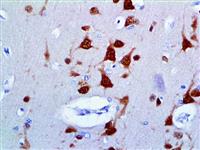

NeuN (Feminizing Locus on X-3, Fox-3, or Hexaribonucleotide Binding Protein-3) is a neuron-specific protein that is present in most Central Nervous System (CNS) and Peripheral Nervous System (PNS) neuronal cell types. NeuN protein distributions are restricted to neuronal nuclei, perikarya and some proximal neuronal processes in both fetal and adult brain. However, some neurons fail to be recognized by NeuN at all ages, such as INL retinal cells, Cajal-Retzius cells, Purkinje cells, inferior olivary and dentate nucleus neurons, and sympathetic ganglion cells.

NeuN antibody is widely used to label neurons since the vast majority of neurons are strongly positive. NeuN immunoreactivity becomes obvious as neurons mature, typically after they have downregulated expression of Doublecortin, a marker seen in the earliest stages of neuronal development.